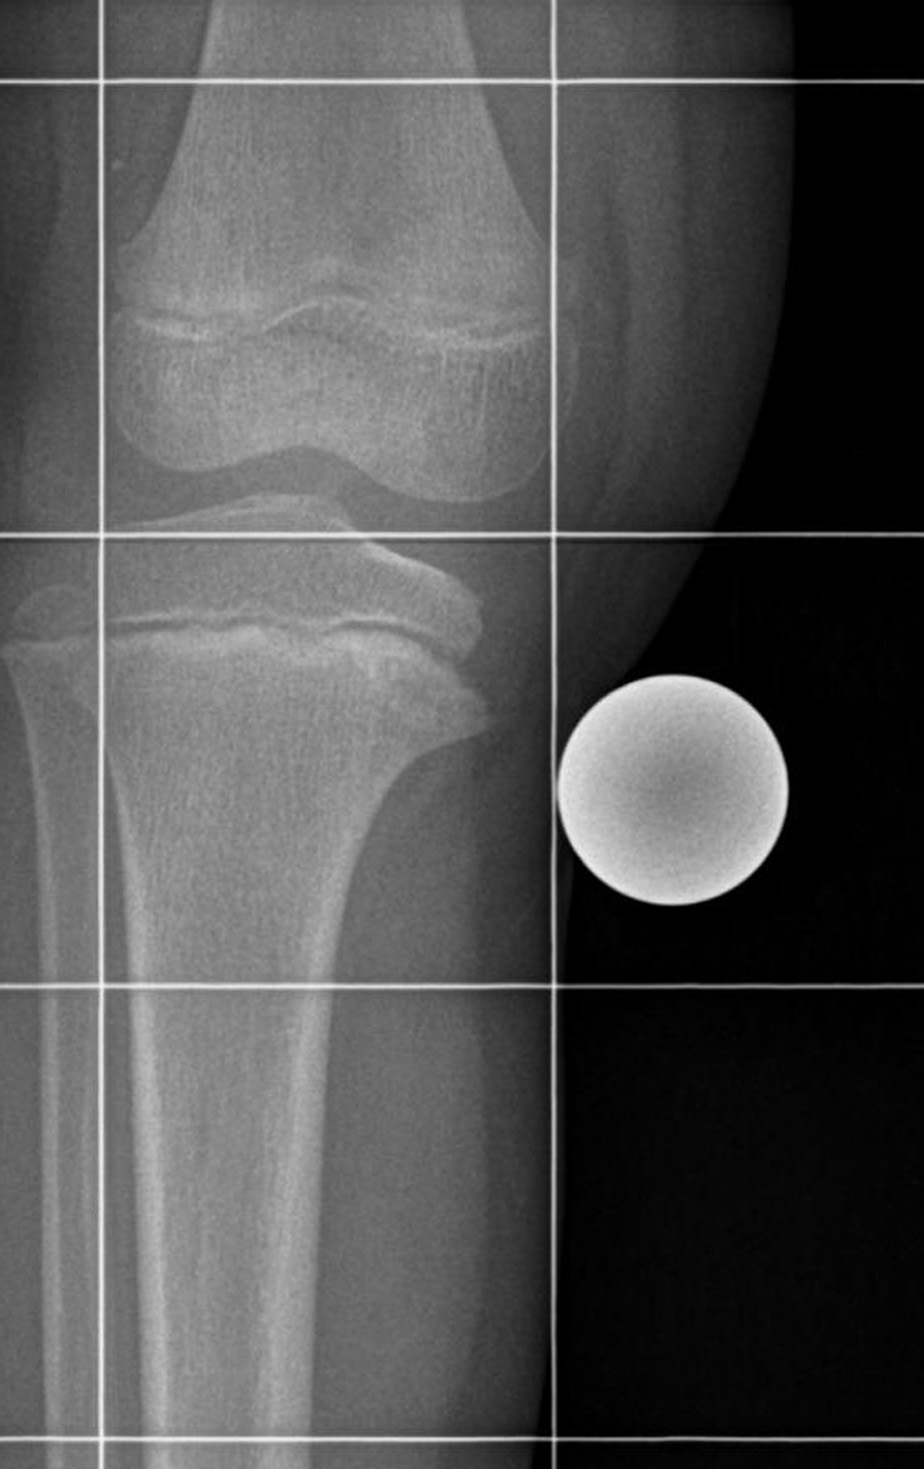

Ein Kniekiller: die Osteochondrosis dissecans. Die „Gelenkmaus“ hängt im medialen Kondylus. Ein Kniekiller: die Osteochondrosis dissecans. Die „Gelenkmaus“ hängt im medialen Kondylus. © wikimedia/nomen 49